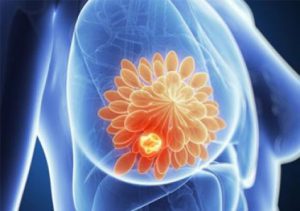

علائم سرطان سینه و نشانه های اولیه آن چیست؟

سرطان سینه یا پستان چیست؟ (علت، علائم، راههای درمان آن)

علت سرطان سینه چیست؟

علائم سرطان سینه چیست؟